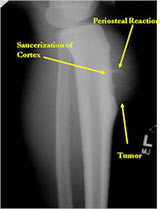

Radiographic imaging is used to help form a diagnosis. These include X-Ray, MRI, CT and Bone Scans

An example of an X-Ray is shown.